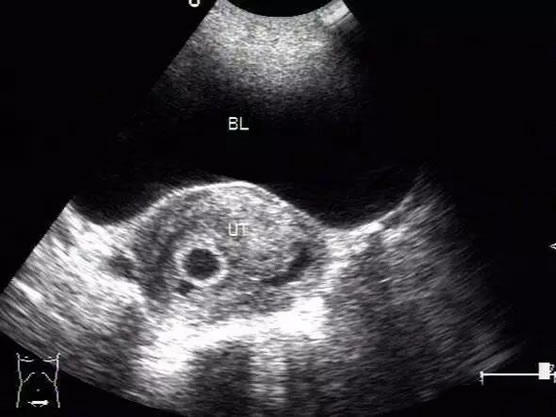

【孕囊】孕7-9周会做第一次b超,确定是不是宫内和胎压胎心率。这个大家都很熟悉。判别的方法是圆形的孕囊代表女孩,长椭圆形的孕囊代表男孩。